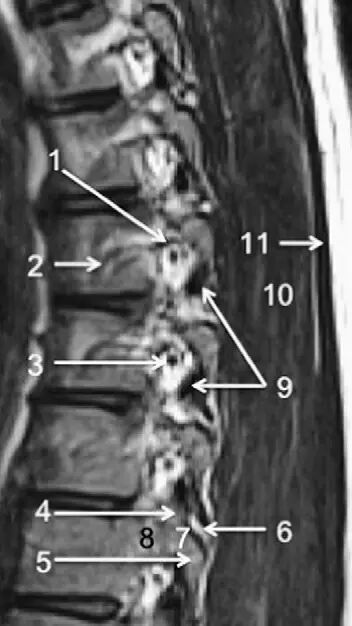

图1正常脊椎的MRI检查,左图为正中矢状位T2WI,右图为T1WI图 2 胸椎 T2WI 轴位图:1,肋椎关节;2,类骨头;3,黄韧带;4,椎弓根;5,椎弓板;6,横突;7,棘突;8,肋横突关节;9,肋结节;10,半奇静脉;11,后纵韧带图 3 腰椎矢状位 T1WI 序列成像:1,脊髓;2,脊髓圆锥;3,马尾;4,蛛网膜下腔;5,硬膜外脂肪;6,黄韧带;7,棘间韧带;8,棘上韧带;9,椎体静脉丛;10,硬膜外静脉丛;11,硬膜外脂肪;12 主动脉图 4 L5/S1 水平轴位 T1WI 序列成像:1,腰肌;2,L5 神经根(前支);3,L5 神经根(后支);4,黄韧带;5,蛛网膜下腔;6,马尾神经根;7,小关节面;8,髂腰韧带;9,左髂外静脉;10,左髂外动脉;11,右髂外动脉;12,右髂外静脉;13,多裂肌;14,竖脊肌组图 5 腰椎旁矢状位 T1WI 序列成像:1,腰静脉;2,腰动脉;3,椎间孔静脉;4,脊神经节后根;5,椎间孔静脉;6,关节面;7,多裂肌;8,竖脊肌群;9,胸腰筋膜,后层图 6 胸椎 T1WI 序列成像:1,胸髓;2,蛛网膜下腔;3,硬膜外脂肪;4,黄韧带;5,多裂肌;6,棘突;7,硬膜外静脉;8,棘上韧带图 7 胸椎矢状位 T2WI 序列成像:1,胸髓;2,蛛网膜下腔;3,黄韧带;4,多裂肌;5,棘突;6,棘上韧带;7,椎体静脉;8,脊髓圆锥;9,马尾图 8 胸椎旁矢状位 T2WI 序列成像:1,硬膜囊后壁;2,硬膜外脂肪;3,黄韧带图 9 胸椎轴位 T2WI 序列成像:1,主动脉;2,半奇静脉;3,奇静脉;4,椎间孔静脉;5,胸肋间血管;6,脊神经节后根;7,椎体静脉;8,后纵韧带;9,脑脊液流动伪影;10,多裂肌;11,背最长肌;12,斜方肌图10 胸椎旁矢状位 T2WI 序列成像:1,椎间孔静脉;2,胸椎旁肋间动静脉;3,神经根;4,上关节突;5,下关节突;6,关节面;7,椎弓峡部;8,椎弓根;9,黄韧带;10,竖脊肌群;11,斜方肌——本期完——